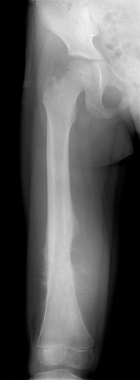

M.D. - 5 year old female with right thigh pain for one month, her parents have noticed swelling in her thigh over the past week, she began limping a few days ago and now is reluctant to bear weight on her right leg

Zoom image: Radiological image Radiological image.

Zoom image: Cell stain Cell stain.